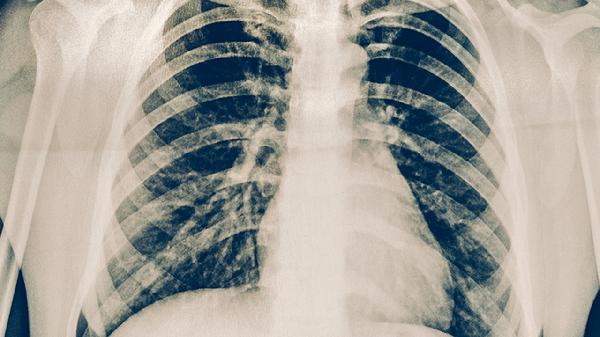

4、影像学表现

肺结核胸部X线可见肺尖或上叶后段浸润影、空洞形成或钙化灶,普通咳嗽胸片多显示肺纹理增粗或无异常。肺结核可能伴随纵隔淋巴结肿大,普通肺炎多表现为斑片状阴影且病灶局限。